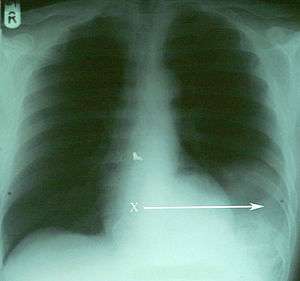

| An X-ray showing the spleen in the left lower portion of the chest cavity (X and arrow) after a diaphragmatic tear[1] | |